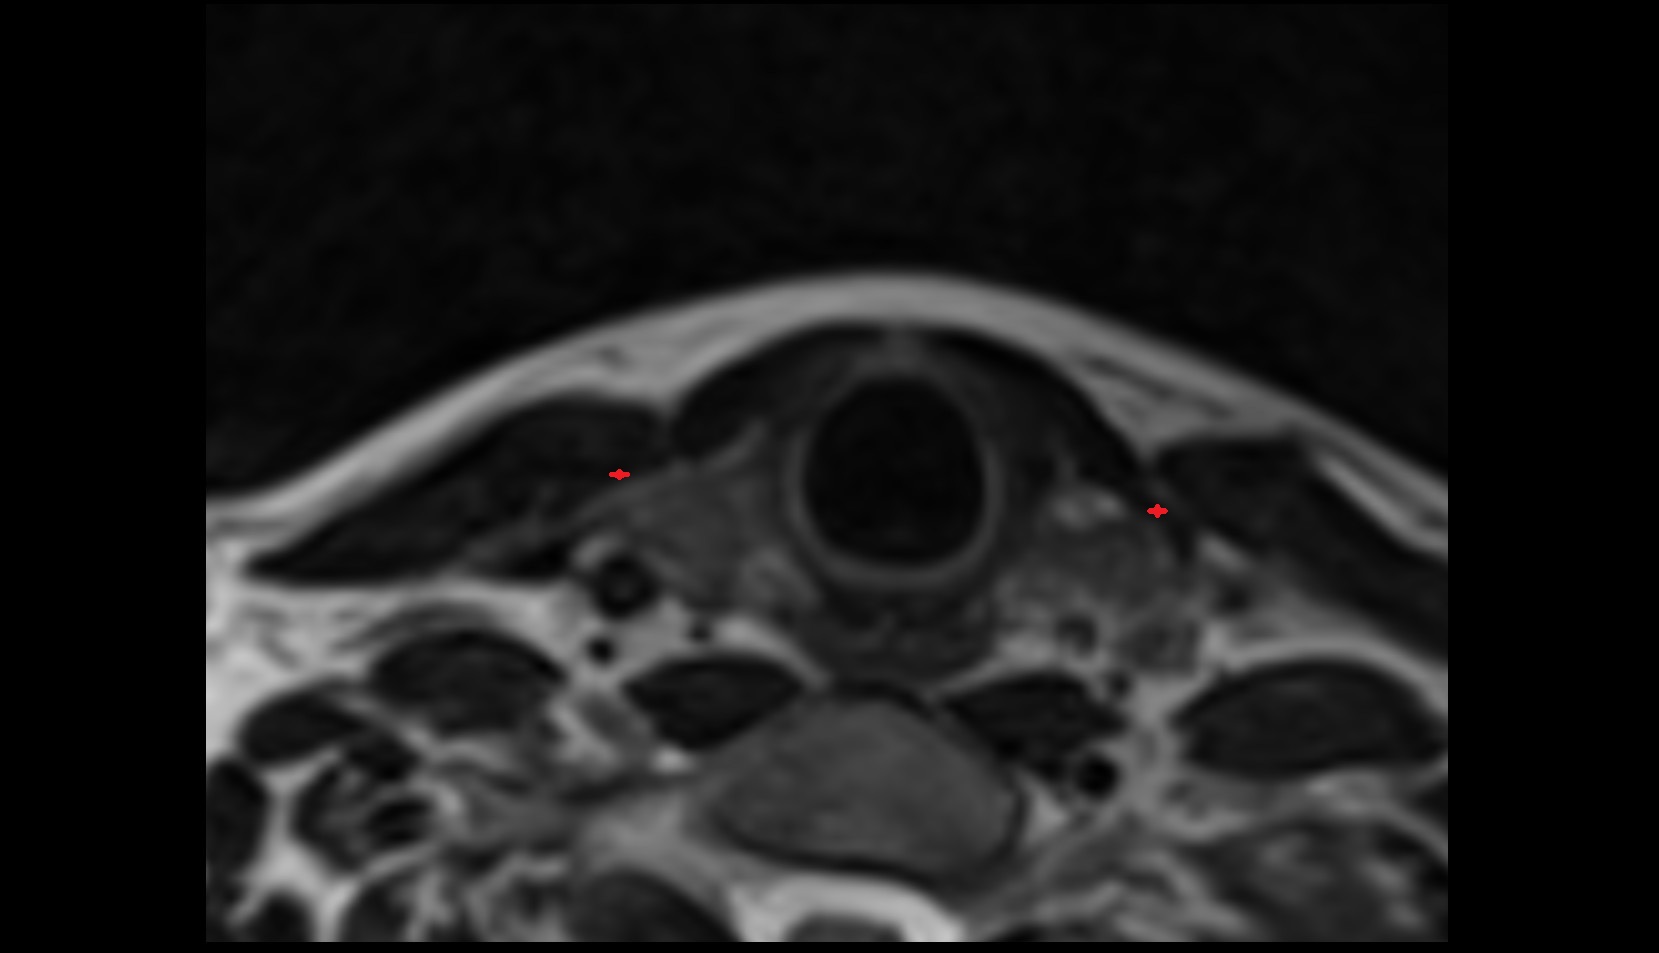

- Internal carotid artery (cervical part)

- Right vertebral artery (cervical part)

- Left vertebral artery (cervical part)